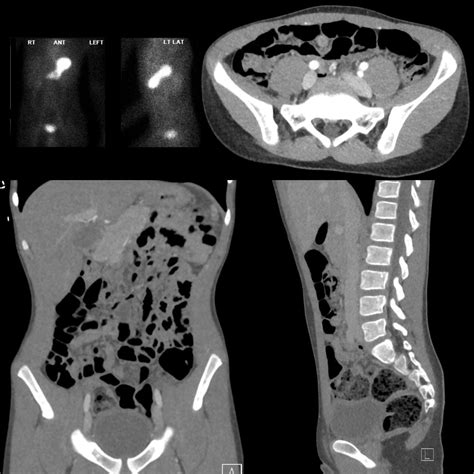

A Meckel’s Diverticulum Scan utilizes a radioactive tracer, typically Technetium-99m pertechnetate. This tracer is absorbed by the gastric mucosa cells, making them visible under a specialized camera known as a gamma camera. The procedure is generally broken down into several stages to ensure the highest accuracy:

• Imaging: The patient lies on an imaging table, and the gamma camera is positioned over the abdomen. Images are typically captured continuously for about 45 to 60 minutes to track the movement and localization of the tracer.

The interpretation of a Meckel’s Diverticulum Scan requires expertise in nuclear medicine. A positive result is indicated by a “hot spot”—an area of increased radioactivity that appears in the lower abdomen during the imaging sequence. This “hot spot” corresponds to the area where the technetium-99m has accumulated in the gastric mucosa.

Advancements in Imaging Technology

While the classic scintigraphy remains the primary choice, hybrid imaging techniques are starting to play a larger role. Combining a Meckel’s Diverticulum Scan with Single-Photon Emission Computed Tomography (SPECT) can provide 3D anatomical localization. This added depth helps surgeons better prepare for potential removal of the diverticulum, ensuring that the procedure is as minimally invasive as possible. By improving the precision of the diagnostic map, physicians can reduce the need for exploratory abdominal surgery.